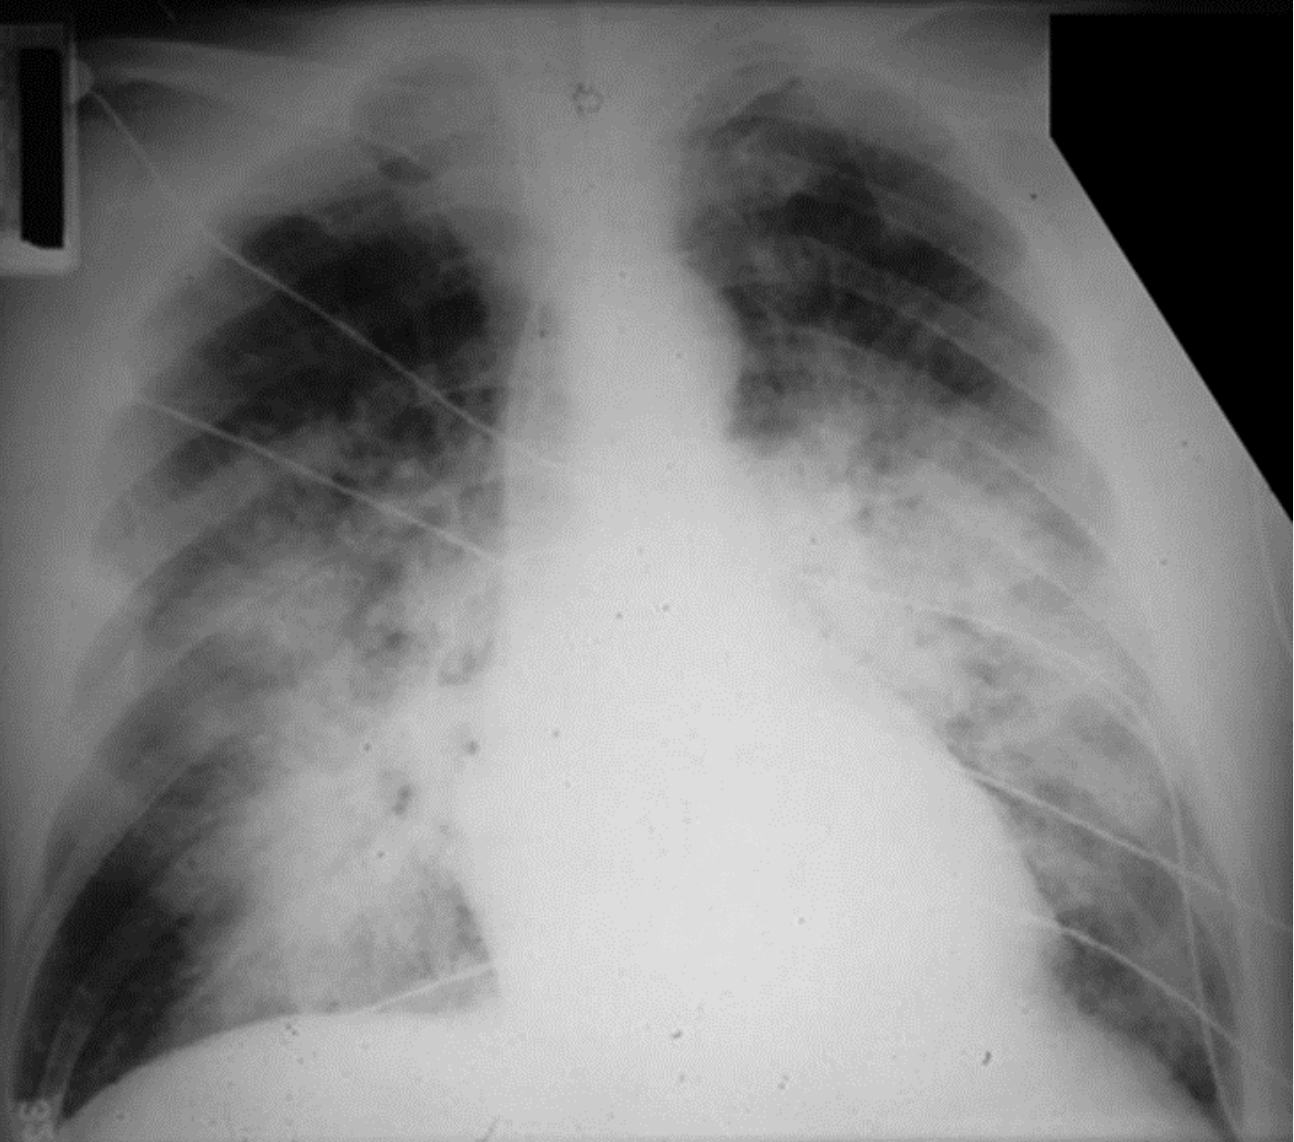

10

Q

?

A

Acute respiratory distress syndrome

- normal heart

-no pleural effusion

-bilateral widespread pulmoonary inflitrates

-air bronchograms